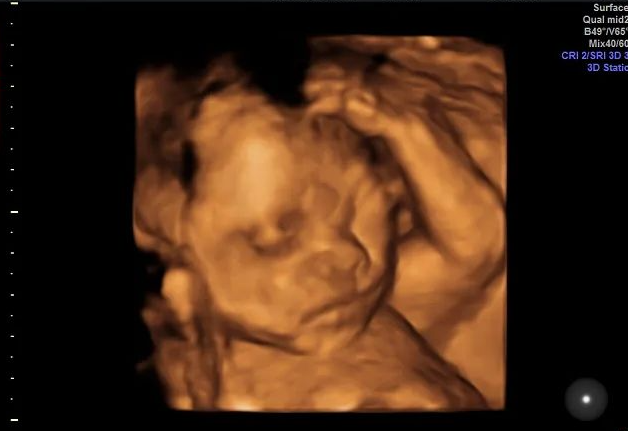

大畸形筛查也就是宝妈们俗称的“大排畸”、“四维彩超”,是孕中期一项不能忽视,且一定要做的重要检查。

它不仅可以全面检查宝宝的各器官是否存在结构缺陷,还能排除重大心脏畸形,同时还能让宝爸宝妈在屏幕中与宝宝“会面”,可以说,这是一项相当令宝爸宝妈期待的检查项目了。

做大畸形筛查,单胎的宝妈一般建议在孕20-24周,双胎在孕20-22周,因为在这个时间段,宝宝的羊水充足,在宝妈肚子里活动空间较大,宝宝大部分器官在超声下都可以观察到,大畸形筛查时能够系统完整的检测宝宝的生理发育情况,也有利于进行胎儿体表筛查。